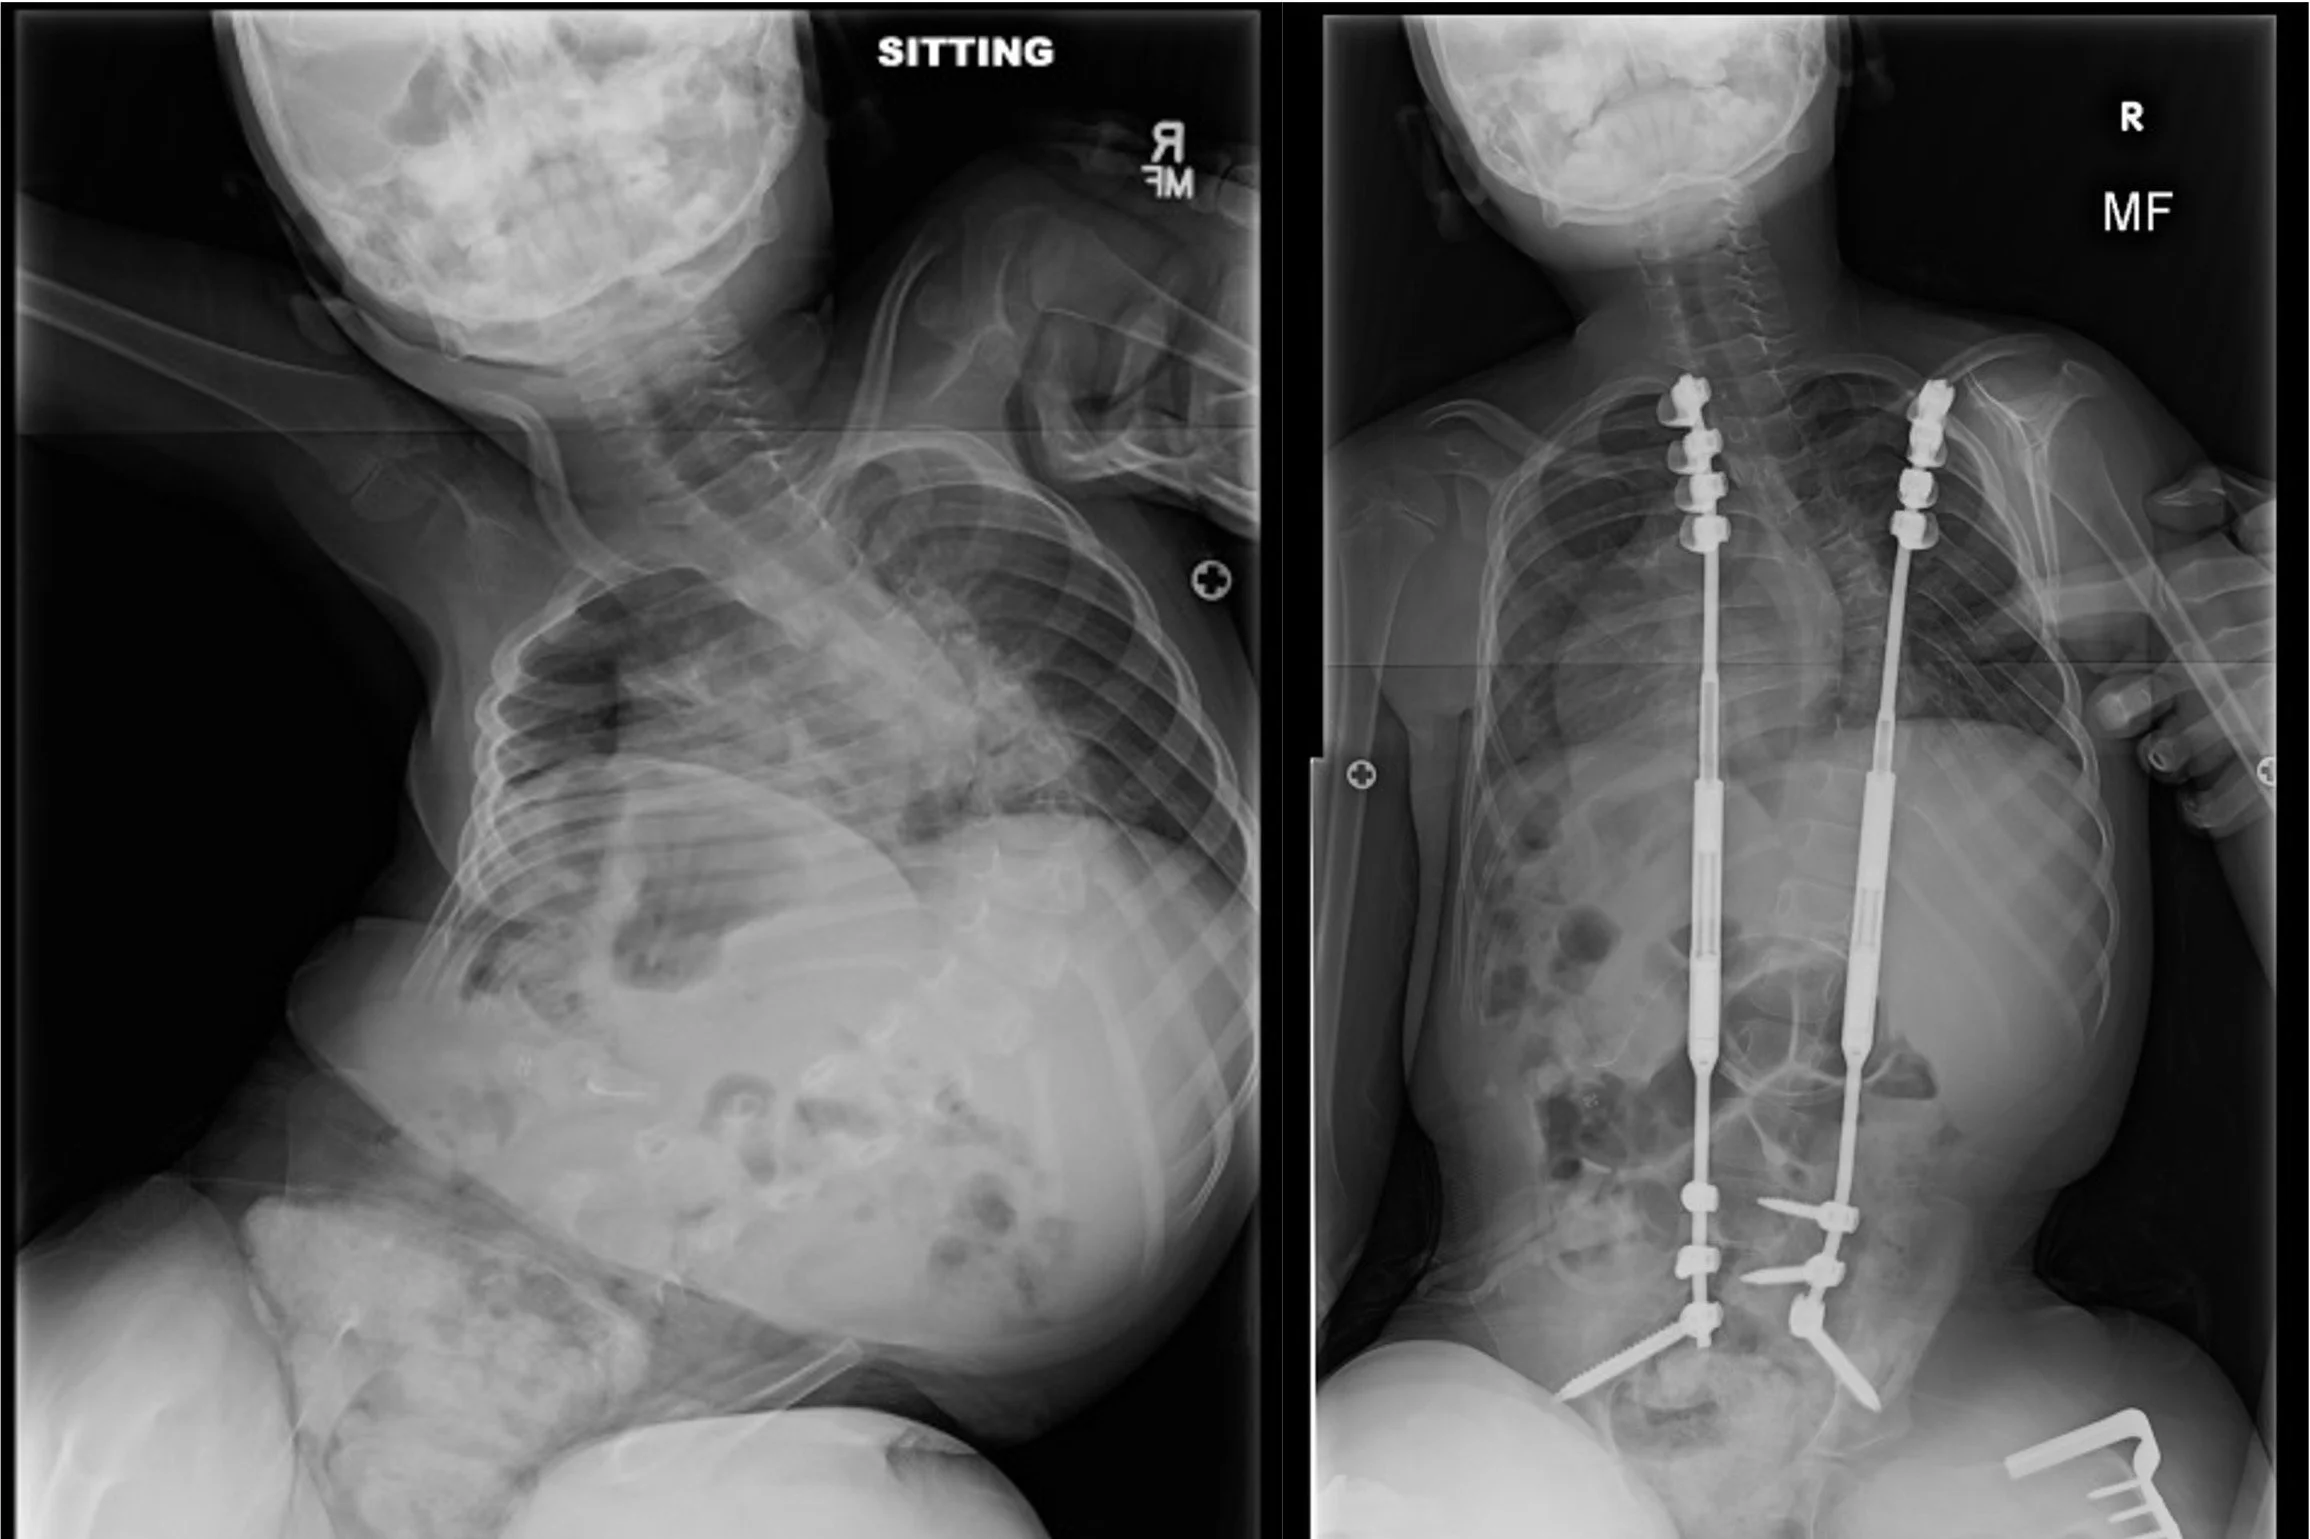

Growing Instrumentation

Young patients, who have large curves, sometimes require early intervention in order to improve the curve size, prevent it from getting worse, and allow for continued spinal growth to optimize lung development. Magnetically controlled growing rods allow these rods to be lengthened in the clinic with a magnet and avoids repeat surgeries.